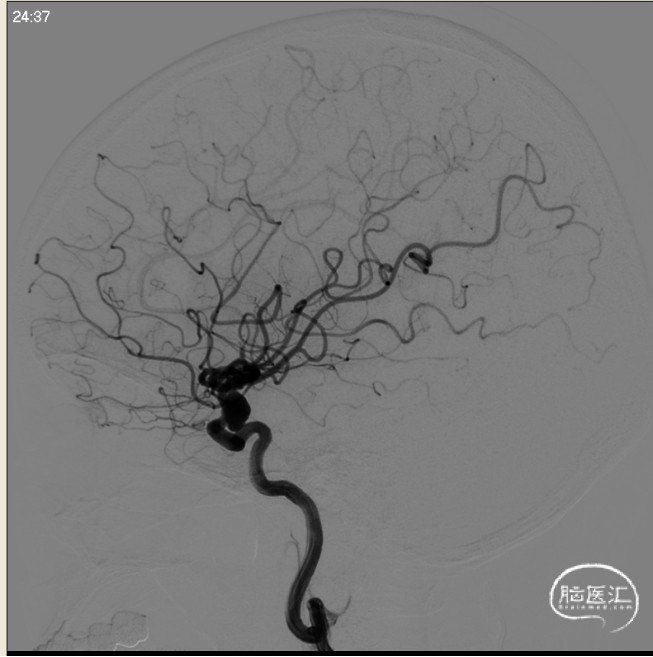

术前左侧侧位

术前左侧正位

术前右侧正位

术前右侧侧位

术前工作位

左侧3D

右侧3D

取右侧股动脉为穿刺点,Seldinger法穿刺成功后置入6F鞘。行全脑血管造影显示左侧颈内动脉眼动脉段动脉瘤,约10*7mm大小,瘤颈6.1mm。6F 90长鞘+115cm 6F SKATHI中间导管超选至左侧颈内动脉海绵窦段。